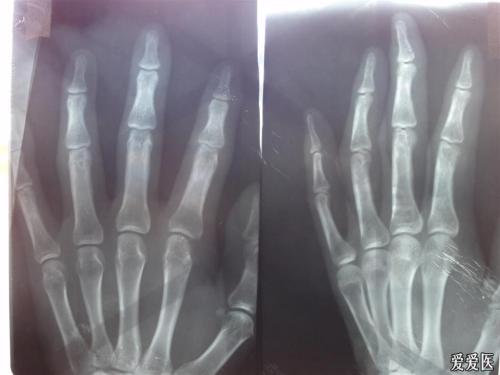

依据关节炎症状选择药物。关节炎的类型分为非对称性少数关节炎、脊柱炎、类风湿样关节炎、远端指(趾)关节炎及致残性关节炎等,不同类型的关节炎选择治疗的药物也不同,某些抑制剂对周围型关节炎效果较好,药物的使用,切不可盲目,要在广州治疗牛皮癣医院听从专业专业的医生指导和建议,以免用药不当造成不良的影响或伤害。

并发脓疱型银屑病或红皮病型银屑病。关节型银屑病和脓疱型银屑病或红皮病型银屑病复杂,常伴有发热、贫血等症状,类风湿因子呈阴性,低钙值,可并发内脏损害如淀粉样变,溃疡性结肠炎等其他危害。

除了银屑病关节炎,类风湿性关节炎也常发生。伴有关节肿胀疼痛、活动受限、关节僵硬、关节积液或变形等临床表现。在很长一段时间后,关节会僵硬。应确定与类风湿关节炎相比,这是更接近小关节的侵入,但不伴有牛皮癣,类风湿因子阳性。